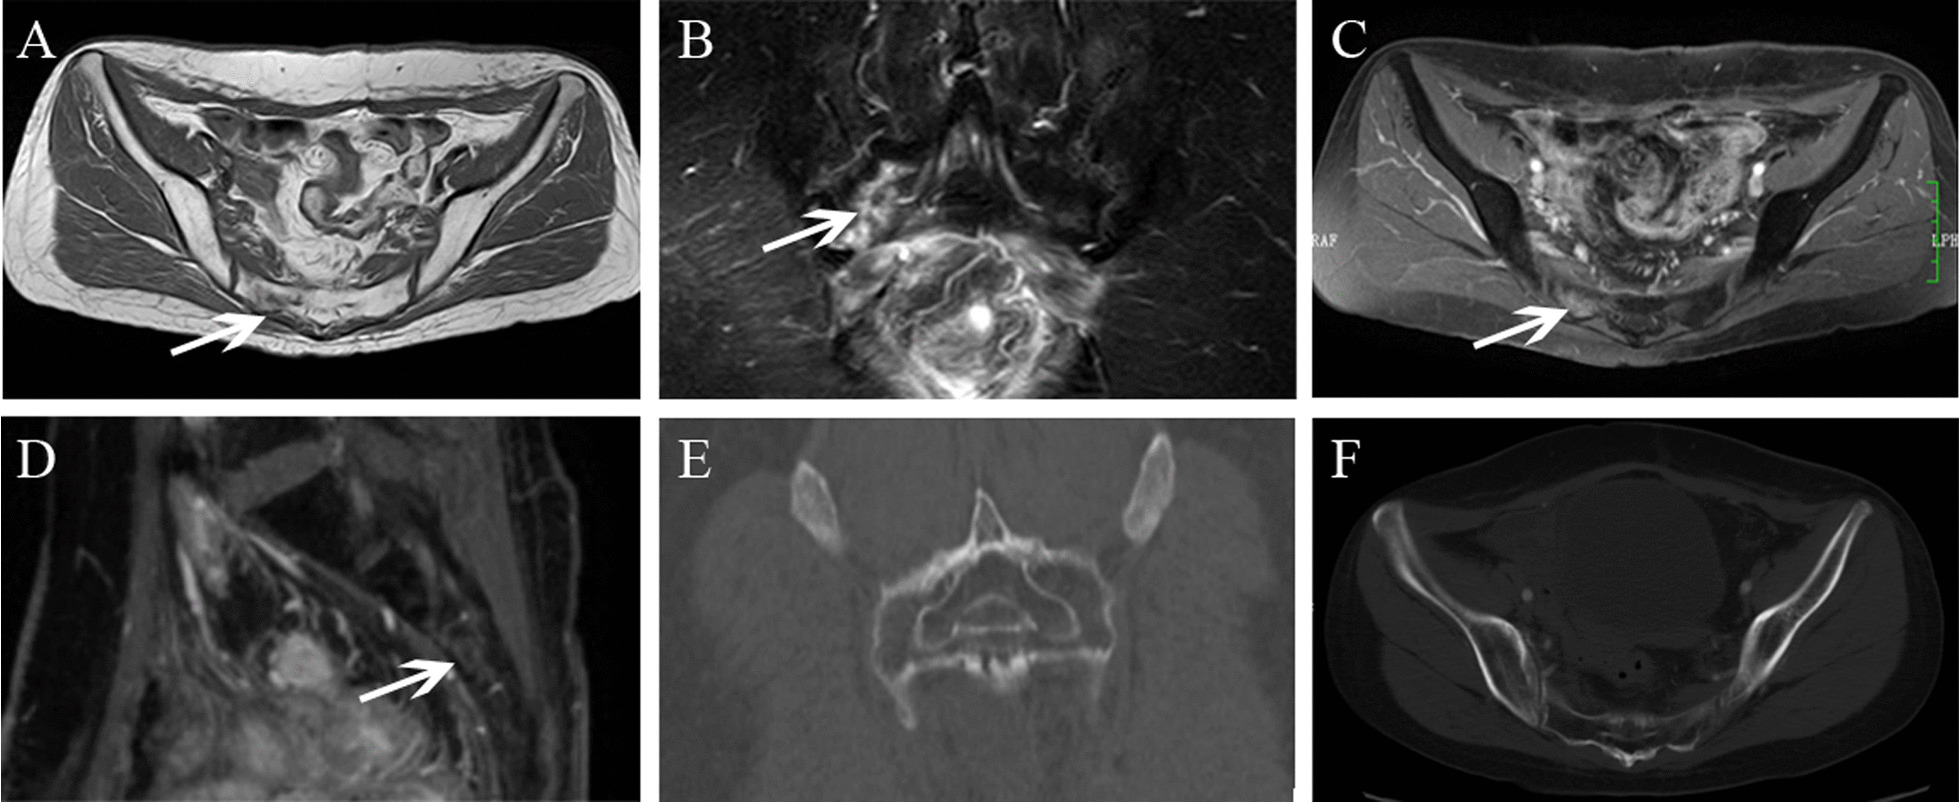

Fig.3.

Bilateral SIFs had coexistent L5, acetabulum fractures in a 68-year-old woman with cervical cancer after radiotherapy. A, B Axial TWI and enhanced T1WI showed right sacrum abnormal signal (arrow). C Coronal FS-T2WI showed abnormal signal in bilateral sacrum, right sacrum showed severe bone marrow edema, and left sacrum showed mild bone marrow edema (arrow). D, E Coronal FS-T2WI showed acetabulum and L5 fractures. F Coronal CT image showed osteosclerosis change in L5 and right sacrum

Fig.4.

Bilateral SIFs had coexistent bilateral ilium fractures in a 70-year-old woman with cervical cancer after radiotherapy. A, B Axial T1WI and T2WI showed bilateral sacrum low signal (arrow). C Coronal FS-T2WI showed bilateral sacrum and ilium hyperintensity, bilateral sacrum with severe bone marrow edema. D Axial enhanced T1WI showed mild contrast enhancement in bilateral sacrum. E, F. Axial and coronal CT image showed osteosclerosis change